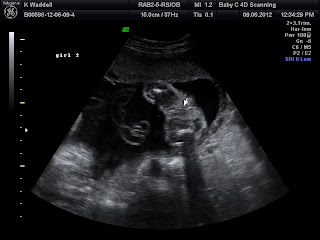

I went for a fun 3D/4D Ultrasound last Sat. The sonographer thinks they are identical twins. She only sees one placenta, but when I asked if it could have been possible that there were two and they fused, she said yes. She says there are other signs that point to identical as well. She said the thin membrane separating the babies is in the shape of a lambda sign, which is common with identical twins. Fraternal twins usually have a T sign. Not sure why though.

Anyways, the Dr. thinks probably fraternal and the sonographer thinks most likely identical! huh! We'll only know for sure after they are born.

We've also confirmed 3 times that they are both girls!!! They are measuring just a tad small, but with in normal limits. She checked everything from brain, heart, stomach, kidneys, bladder, spine, umbilical cord, fluid levels...everything! No problems so far. No cleft palate or club foot either and they each have 10 fingers and 10 toes each! This sonographer was VERY thorough! We really liked her. :)

Baby Girl B at 24.5weeks....

Look closely at the U/S photo below! This is what we all think is funny....girl B's face is right up in Girl's A's butt! Girl B's hands are up blocking her sister's butt from her face!!! LOL

Baby Girl B at 24.5weeks!

Girl B's heart rate = 163bpm